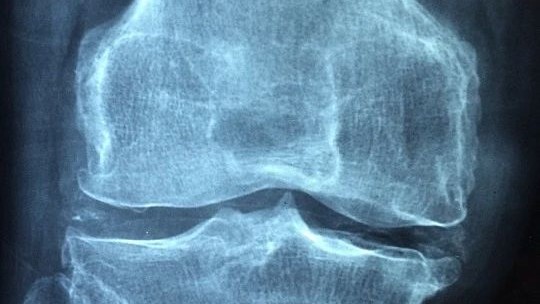

骨質疏鬆症是中老年人群必須要面對的重要健康問題,有統計顯示,50歲以上男性骨質疏鬆症患病率為6.0%,女性患病率則達到32.1%,65歲以上女性的骨質疏鬆症患病率更是達到51.6%。此外,還有大量人群骨量非常低,成為骨質疏鬆症的“後備大軍”。

骨質疏鬆其實是一種全身性疾病,根據病因的不同可以分為三類,第一大類是與絕經、年齡大有關的,稱為原發性骨質疏鬆,多見於中老年人。第二大類是與疾病或藥物有關,稱為繼發性骨質疏鬆,常見的一些疾病如甲亢、1型糖尿病、肝膽疾病、類風溼、痛風、慢性腎病等,以及一些藥物如糖皮質激素、肝素、甲氨蝶呤等,均會導致骨質疏鬆,這一類可見於任何年齡段。最後還有一類是特發性骨質疏鬆,與骨代謝調節異常有關,比如青春期生長,或者妊娠期及哺乳期,“需求”突增,骨形成和吸收的平衡被打破,也會導致骨質疏鬆。